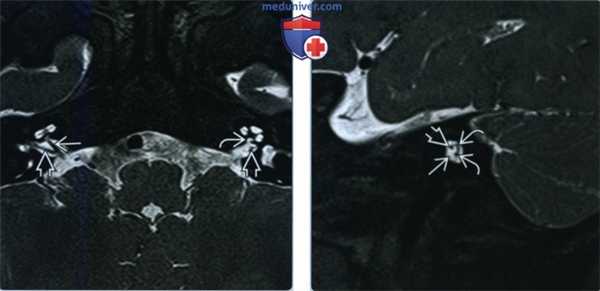

(Слева) При аксиальной КТ в костном окне у мальчика в возрасте 2,5 лет с глубокой двухсторонней врожденной нейросенсорной тугоухостью визуализируется маленькая бутонообразная структура, сопоставимая с гипоплазией улитки, изолированная от внутреннего слуховою канала (ВСК). Круглое окно отсутствует.

(Справа) При корональной КТ (реконструкция) у этого же пациента визуализируется маленькая зачаточная улитка (гипоплазия) без внутренней архитектуры.

(Слева) При 3D МРТ Т2 SPACE у младенца мужского пола с глубокой двухсторонней нейросенсорной тугоухостью визуализируется единственный округлый завиток улитки без стержня.

(Справа) На более каудальном изображении у этого же ребенка визуализируется передний край единственного завитка улитки. ВСК и нижний вестибулярный нерв выглядят нормальными. Улитковый нерв не визуализируется, канал улиткового нерва отсутствует.